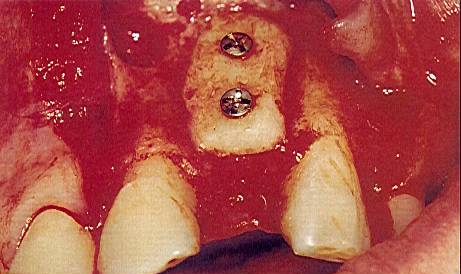

Мост был использован в качестве временного протеза для предотвращения нагрузки на блок на период его приживления. Через 4 месяца после операции было выполнено повторное вмешательство для установки имплантата. Аутотрансплантат подвергся минимальной резорбции (рис. 9). Фиксирующие шурупы были удалены, область подготовлена для установки имплантата 3,75 мм х 16 мм (Screw-Vent) (рис. 10).

Рисунок 9. Прижившийся аутотрансплантат (через 4 месяца). Отсутствие значительной резорбции, сохранена плотная морфология.

Рисунок 10. Удаление фиксирующих шурупов и установка имплантатов длиной 16 мм (сплав титана, Screw-Vent).